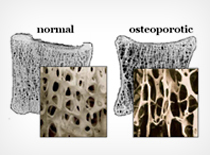

A significant percentage of bone fractures occur because of high force impact or stress; however, a fracture may also be the resultof some medical conditions which weaken the bones, for example osteoporosis, some cancers or osteogenesis imperfecta. A fracture caused by a medical condition is known as a pathological fracture.

Your bones are some of the strongest tissues in your body. If an impact or a force is stronger than the strength of the bone on which it is acting, then a fracture may result. The most common causes of fracture are falls, motor vehicle accidents, and a weakening of the bone called osteoporosis.

» Osteoporosis (thinning and weakening of the bones)